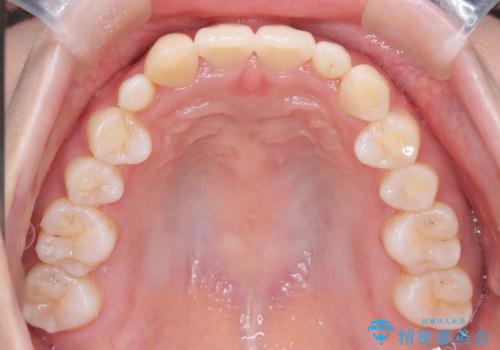

【インビザライン】八重歯が気になる

- 乳歯を抜歯してスペースを確保し八重歯の改善を行いました。

インビザラインをしっかり使用していただいたので、きれいな歯並びになりました。